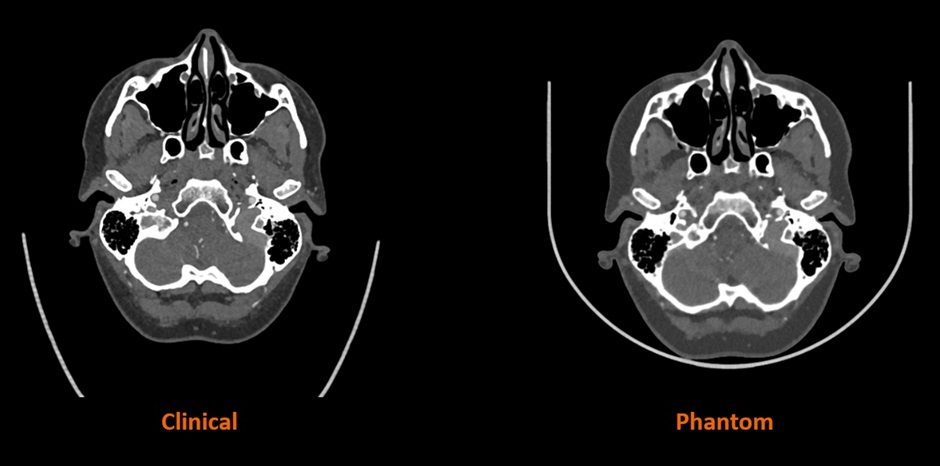

Stratasys 与西门子医疗合作的早期研究结果表明,RadioMatrix 人体模型能够以极高的精度在 CT 成像中复制人体组织,即使在灰质和静脉等敏感区域,偏差也仅为 1 个亨氏单位 (HU)。结合Stratasys 的数字解剖技术和先进的成像算法,最终生成的模型既保留了解剖和病理细节,又为基于尸体的培训提供了一种一致且符合伦理的替代方案。预计这些模型将帮助放射科医生改进和验证 CT 扫描方案,同时加快高级成像算法的创建,从而实现更准确的诊断和治疗计划。

△人体CT扫描与Stratasys公司3D打印模型CT扫描对比。图片来自Stratasys公司。